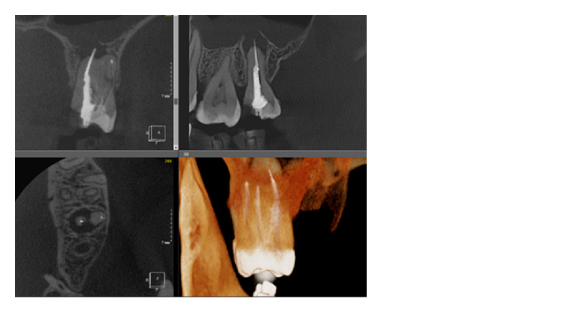

По сути воксель – это структурная единица изображения. Компьютерная томограмма состоит из вокселей, и их размер определяет качество снимка. Как правило, чем меньше FOV снимка, тем меньше и размер вокселя, а это, в свою очередь, делает изображение более качественным (рис. 3). Разные фирмы, производящие дентальные томографы пытаются конкурировать в размерах вокселя, особенно при больших зонах сканирования. Я стараюсь использовать два режима, как правило, это standart definition со средним размером вокселя и high definition с уменьшенным размером вокселя. Если намечается сложная эндодонтия, то, безусловно, high definition с минимальным значением вокселя будет крайне эффективно, но если у пациента огромное количество металла (циркон, металлокерамика и прочее) то порой именно стандартный размер вокселя помогает снизить количество артефактов и сделать изображение более читабельным.

Рис. 3. КЛКТ с зоной сканирования 5x5 см и размером вокселя 70 микрон.